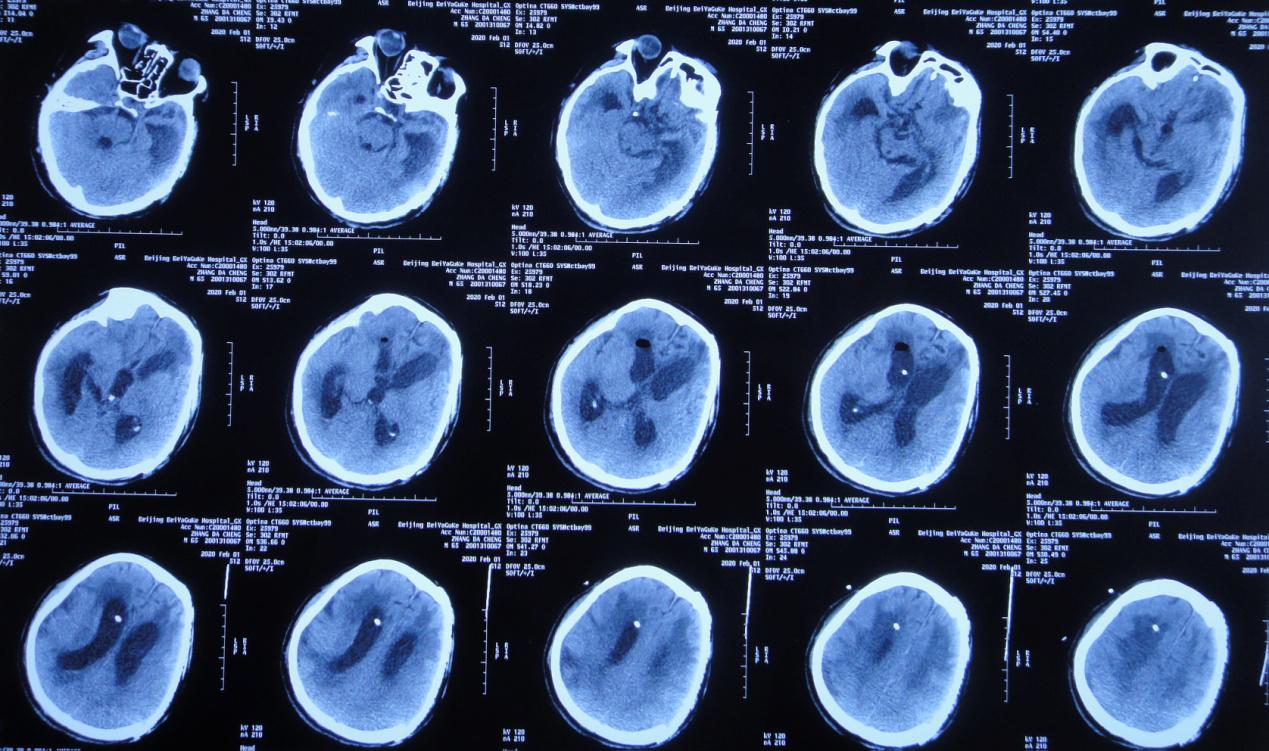

患者意识进一步恶化,颅骨修补术后第34天,即2019年 11月28日,患者意识由嗜睡变为昏睡状态,复查头颅CT( 图-9 )示脑室较前稍增大,脑室周围水肿稍加重。

图-9: 2019年11月28日头颅CT

意识逐渐恶化脑室不断扩大,2019年12月4日行右侧脑室钻孔外引流术,术后当日复查头颅CT( 图-10 )呈脑室钻孔外引流术后改变。

图-10: 2019年12月4日术后头颅CT

更换脑室外引流管后第14天,颅骨修补术后第70天,左颞叶血肿清除+去骨瓣减压术后第176天,即2020年 1月2日,行脑室腹腔分流术(术中拔除原脑室外引流管)。术后第2天复查头颅 CT( 图-11 )呈脑室腹腔分流术后改变。

图-11: 2020年1月4日术后头颅CT

脑室腹腔分流术后第5天,颅骨修补术后第75天,左颞叶血肿清除+去骨瓣减压术后第181天,即2020年 1月7日患者出现高热,体温39.1℃,复查头CT头颅( 图-12 )与2020年1月4日对比未见明显变化。

图-12: 2020年1月7日头颅CT